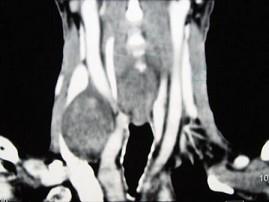

问题 男性,70岁,右侧颈部无痛性肿块3个月,CT扫描如图所示,请选择正确的描述和答案 ( )

选项 A、考虑迷走神经源性肿瘤 B、考虑交感神经源性肿瘤 C、右侧颈静脉被推压至肿块外后方 D、右侧颈动脉被推压至肿块内后方 E、右颈动脉间隙内见类圆形软组织肿块影,密度欠均匀,边缘光整

答案 ACDE